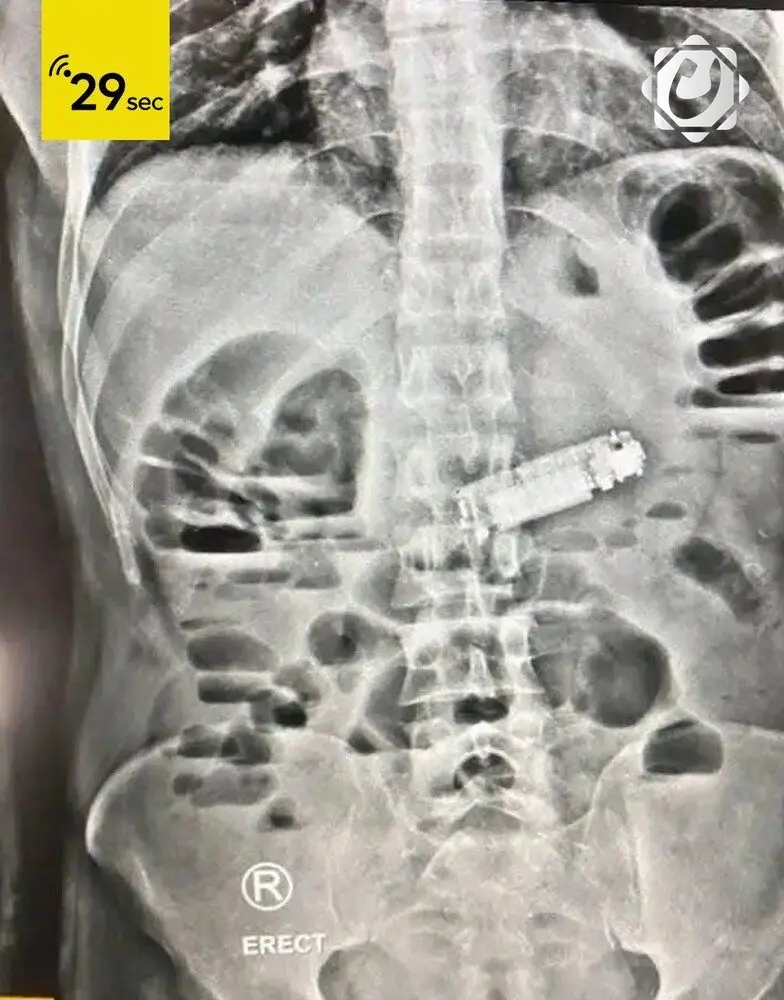

عملية جراحية ناجحة في مستشفى مصري لاستخراج هاتف محمول من معدة مريض